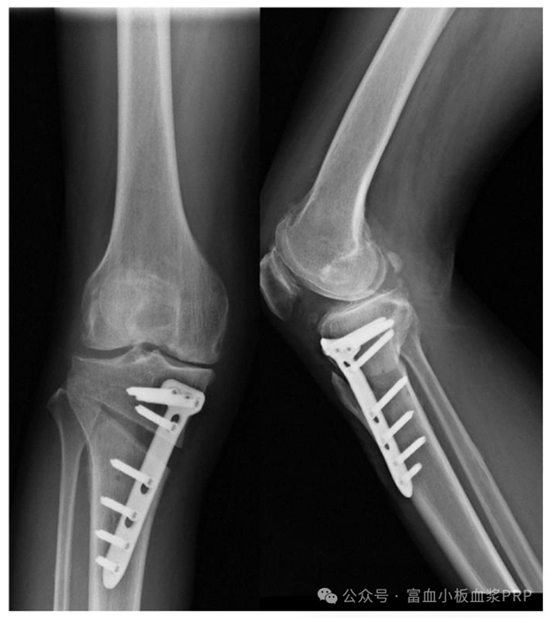

手術 + PRP 注射:先做 HTO 手術(微創(chuàng),切口約 5 厘米),調整膝蓋力線;手術結束前,醫(yī)生會把提前制備好的 PRP 直接注射到關節(jié)腔和截骨部位,然后縫合傷口;